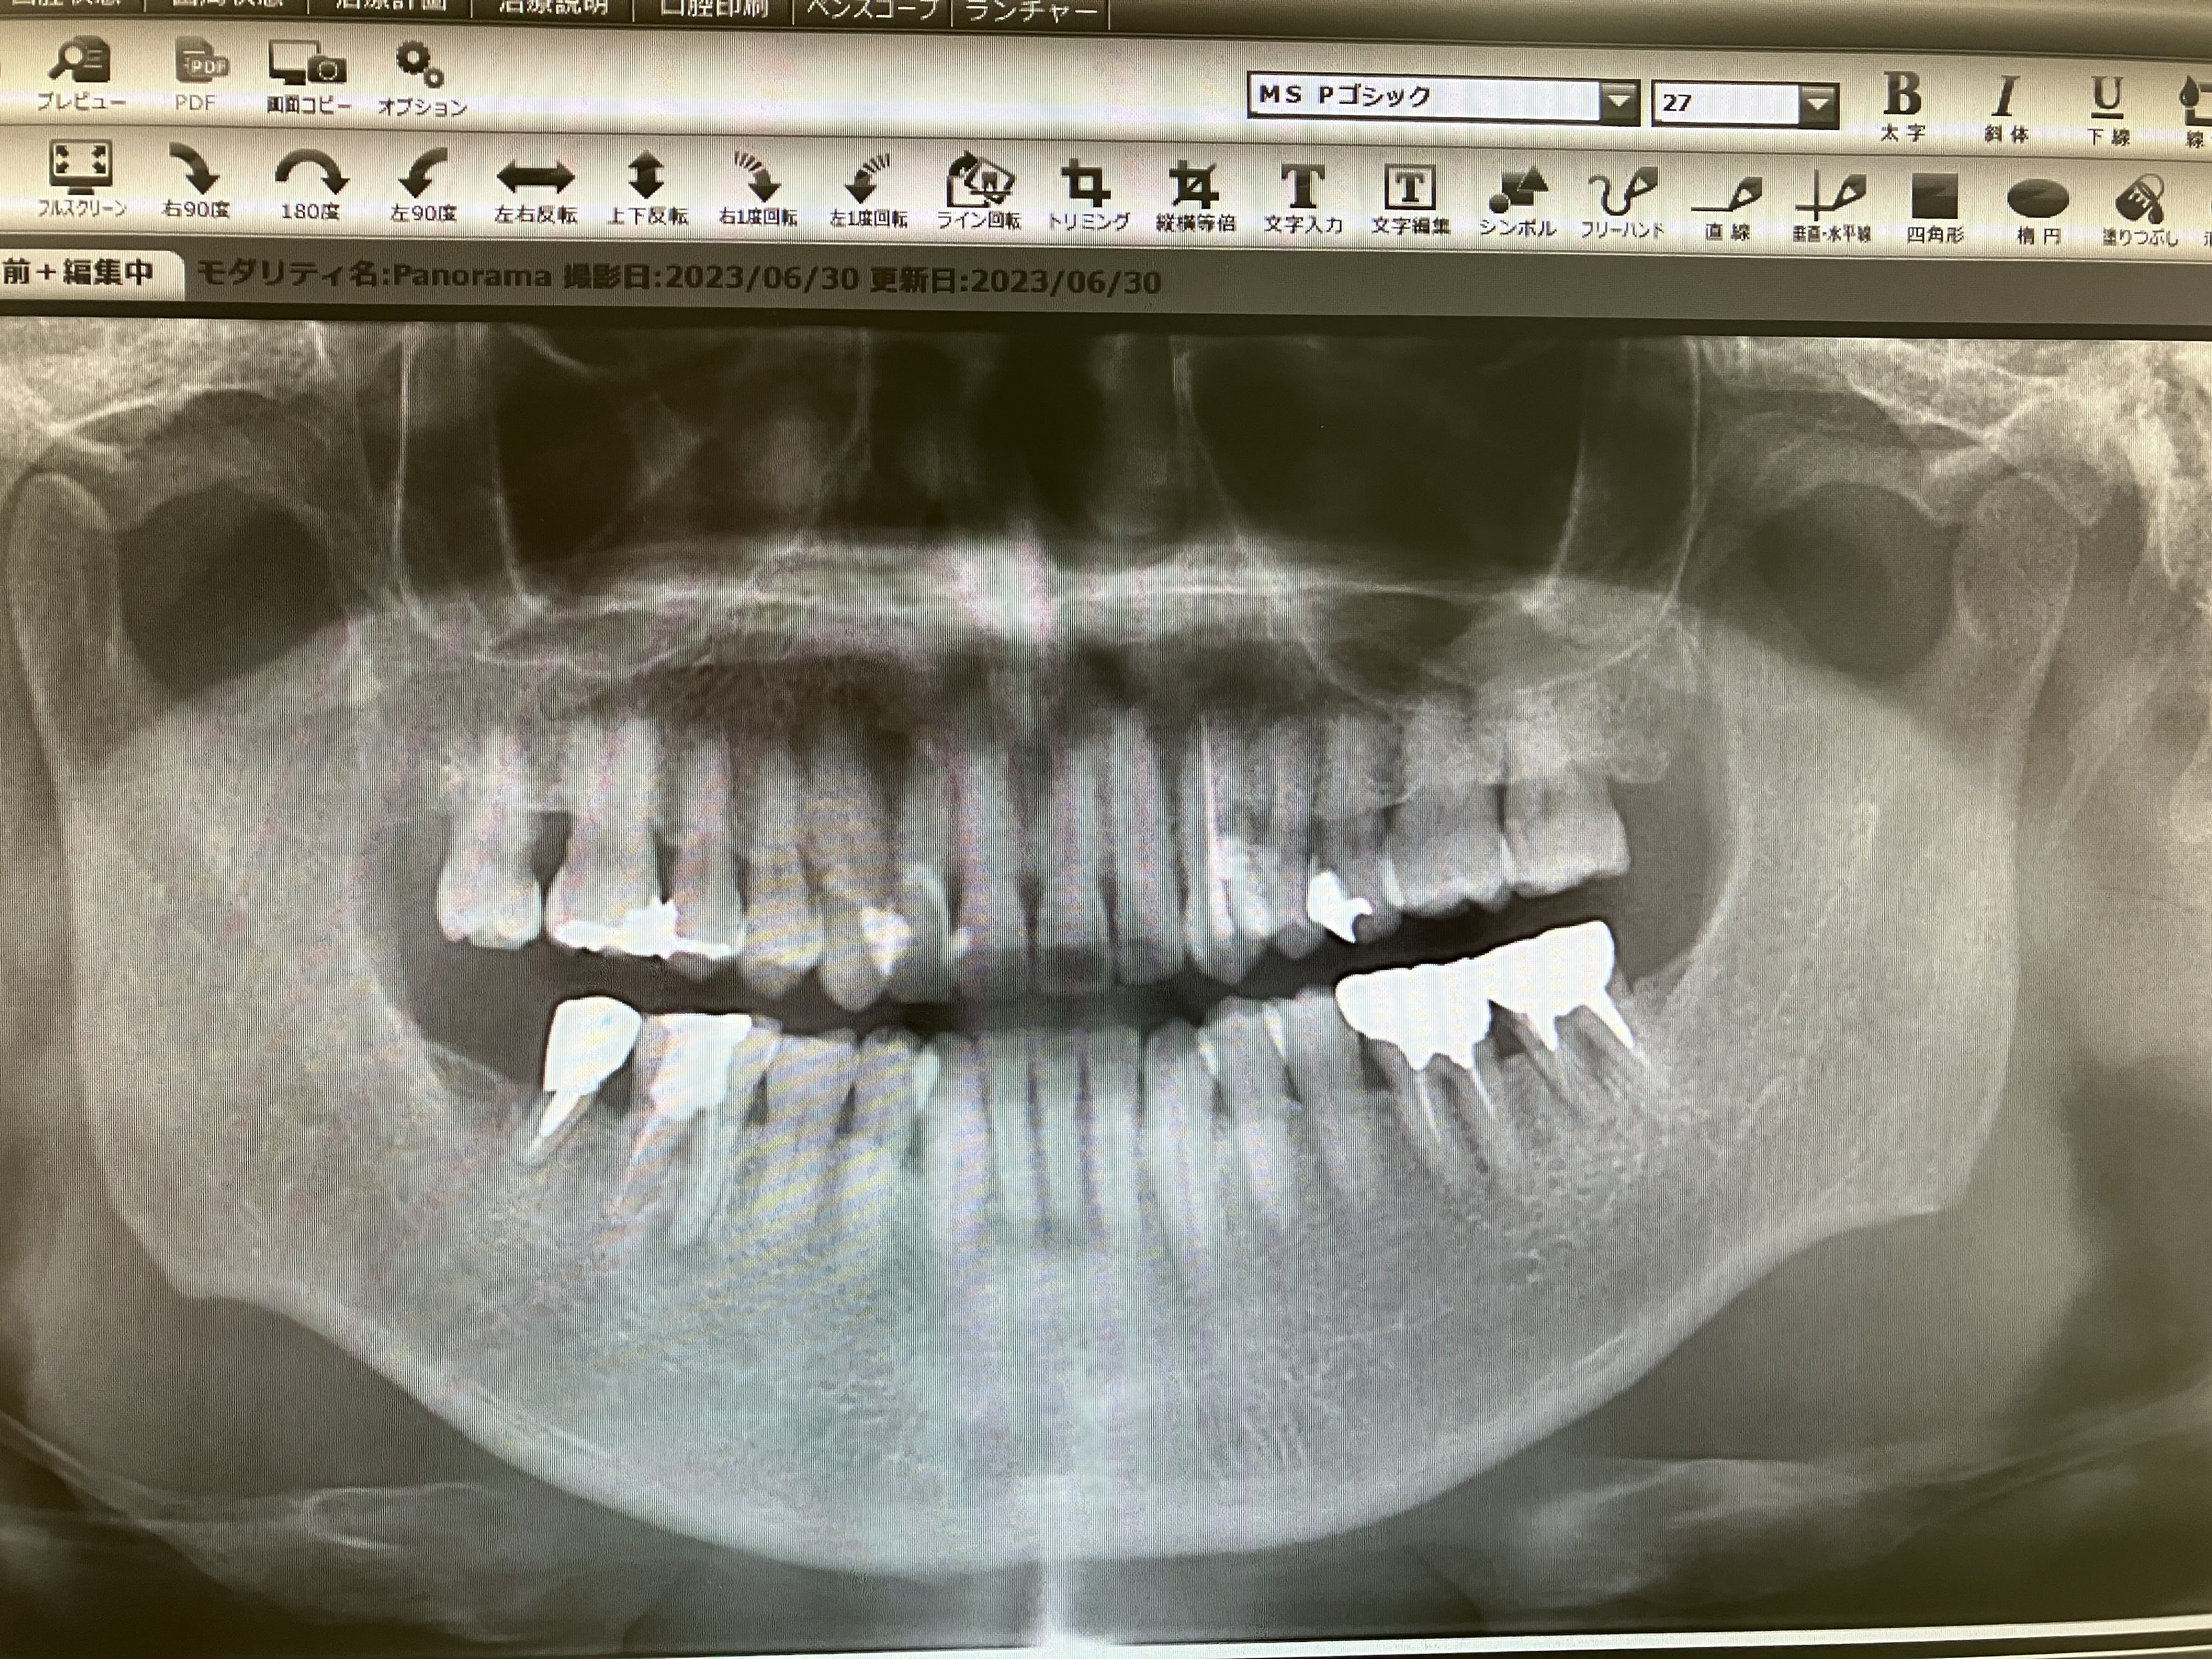

2023.06.30より 圭介歯科 0968-62-1822

2024年7月5日(金) 右上奥歯の虫歯が痛んだ

2024年6月7日(金) 銀冠

23.7.21 検査 PDF   23.10.27 検査 PDF